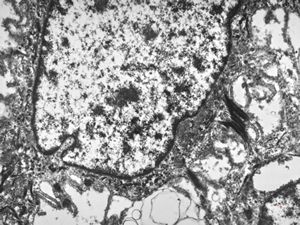

F,41y. | synovial metaplasia - capsule of implantate

F,41y. | synovial metaplasia - capsule of implantate

F,41y. | synovial metaplasia - capsule of implantate

F,41y. | synovial metaplasia - capsule of implantate

F,41y. | synovial metaplasia - capsule of implantate

F,41y. | synovial metaplasia - capsule of implantate

F,41y. | synovial metaplasia - capsule of implantate

F,41y. | synovial metaplasia - capsule of implantate

F,41y. | synovial metaplasia - capsule of implantate